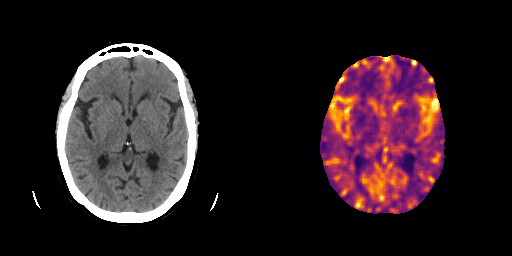

fig:qualitative_ich

ICH

healthy

We show some slices with examples of ICH in \figurereffig:qualitative_ich as well as surface renderings of scans of subjects with cranial fractures in \figurereffig:qualitative_fractures. (As a reference we also included the same examples for the AE in Appendix D in \figurereffig:qualitative_ich_ae.) It is noticeable that the reconstruction error is high where there is an anomaly. The reconstruction error generally seems to continuously depend on the amount of the patch that is anomalous, as the error maps generally seem to be rather smooth.

The performance for the models used for \figurereffig:qualitative_ich and LABEL:fig:qualitative_fractures are shown in \figurereffig:roc_performance. We observe see that the detection of fractures is the more challenging task for our method than the detection of ICH. This might be due to the smaller number of scans available to evaluate it on (see Appendix B). To put these results in context we provided a table with the inter rater agreement on these tasks in Appendix B: The performance in terms of AUROC is around lower than the average raters.